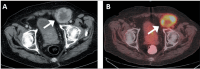

Objective: To investigate clinical, pathology, and imaging findings associated with inguinal lymph node (LN) metastases in patients with prostate cancer (PCa).

Materials and methods: This was a retrospective single-center study of patients with PCa who underwent imaging and inguinal LN biopsy between 2000 and 2023. We assessed the following aspects on multimodality imaging: inguinal LN morphology; extrainguinal lymphadenopathy; the extent of primary and recurrent tumors; and non-nodal metastases. Imaging, clinical, and pathology features were compared between patients with and without metastatic inguinal LNs.

Results: We evaluated 79 patients, of whom 38 (48.1%) had pathology-proven inguinal LN metastasis. Certain imaging aspects- short-axis diameter, prostate-specific membrane antigen uptake on positron-emission tomography, membranous urethra involvement by the tumor, extra-inguinal lymphadenopathy, and distant metastases-were associated with pathology-proven inguinal LN metastases (p < 0.01 for all). Associations with long-axis diameter, fatty hilum, laterality, and uptake of other tracers on positronemission tomography were not significant (p = 0.09-1.00). The patients with metastatic inguinal LNs had higher prostate-specific antigen levels and more commonly had castration-resistant PCa (p < 0.01), whereas age, histological grade, and treatment type were not significant factors (p = 0.07-0.37). None of the patients had inguinal LN metastasis in the absence of locally advanced disease with membranous urethra involvement or distant metastasis.

Conclusion: Several imaging, clinical, and pathology features are associated with inguinal LN metastases in patients with PCa. Isolated metastasis to inguinal LNs is extremely rare and unlikely to occur in the absence of high-risk imaging, clinical, or pathology features.